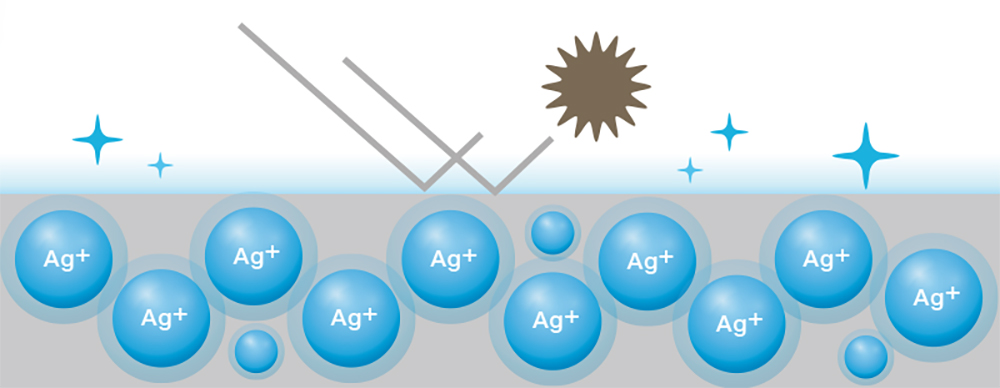

uzun süre dayanan antibakteriyel kaplama

ha2441a’da bulunan çerçeve ve tuşlar antibakteriyel gümüş iyonlu kaplamaya* sahip. bakterilerin tutunmasını %99,9’a kadar önleyen bu kaplama, monitörün önemli bölgelerinin temiz ve hijyenik kalmasını sağlar ve zararlı bakterilerin bulaşma riskini azaltır. asus ha2441a, ıso 22196 faaliyet ve etkinlik testlerini geçmiştir. sonuçlar bağımsız süd test laboratuvarı tarafından doğrulanmıştır.

1. bu özel antibakteriyel kaplama u.s. epa tarafından tescillenmiş ve eu bpr tarafından onaylanmıştır.

2. antibakteriyel tedavi, ıso 22196 standardına göre (plastikler ve diğer gözeneksiz yüzeylerde antibakteriyel aktivitenin ölçümü), antibakteriyel aktiviteye sahip (r) escherichia coli ve staphylococcus aureus içeren bakteri kültürleri kullanılarak bağımsız bir üçüncü taraf laboratuvar tarafından test edilir.

antibakteriyel etkinlik sonucu r > 2. r = 2, işlenmemiş bir yüzeye kıyasla bakteriyel aktivitede %99'luk bir azalmayı gösterir.

gümüş iyonları nasıl çalışır?

pozitif yüklü gümüş (ag+) iyonları, negatif yüklü mikroplar ve bakterilerin hücre duvarlarına bağlanarak işlevini bozar ve yok eder.